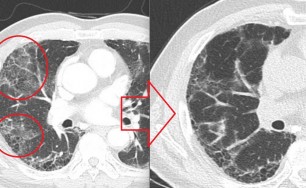

숨케어한의원에서는 전화예약을 받고 있습니다. 내원시 엑스레이, CT사진, 폐기능검사지를 가지고 오시면 자세한 상담이 가능합니다.